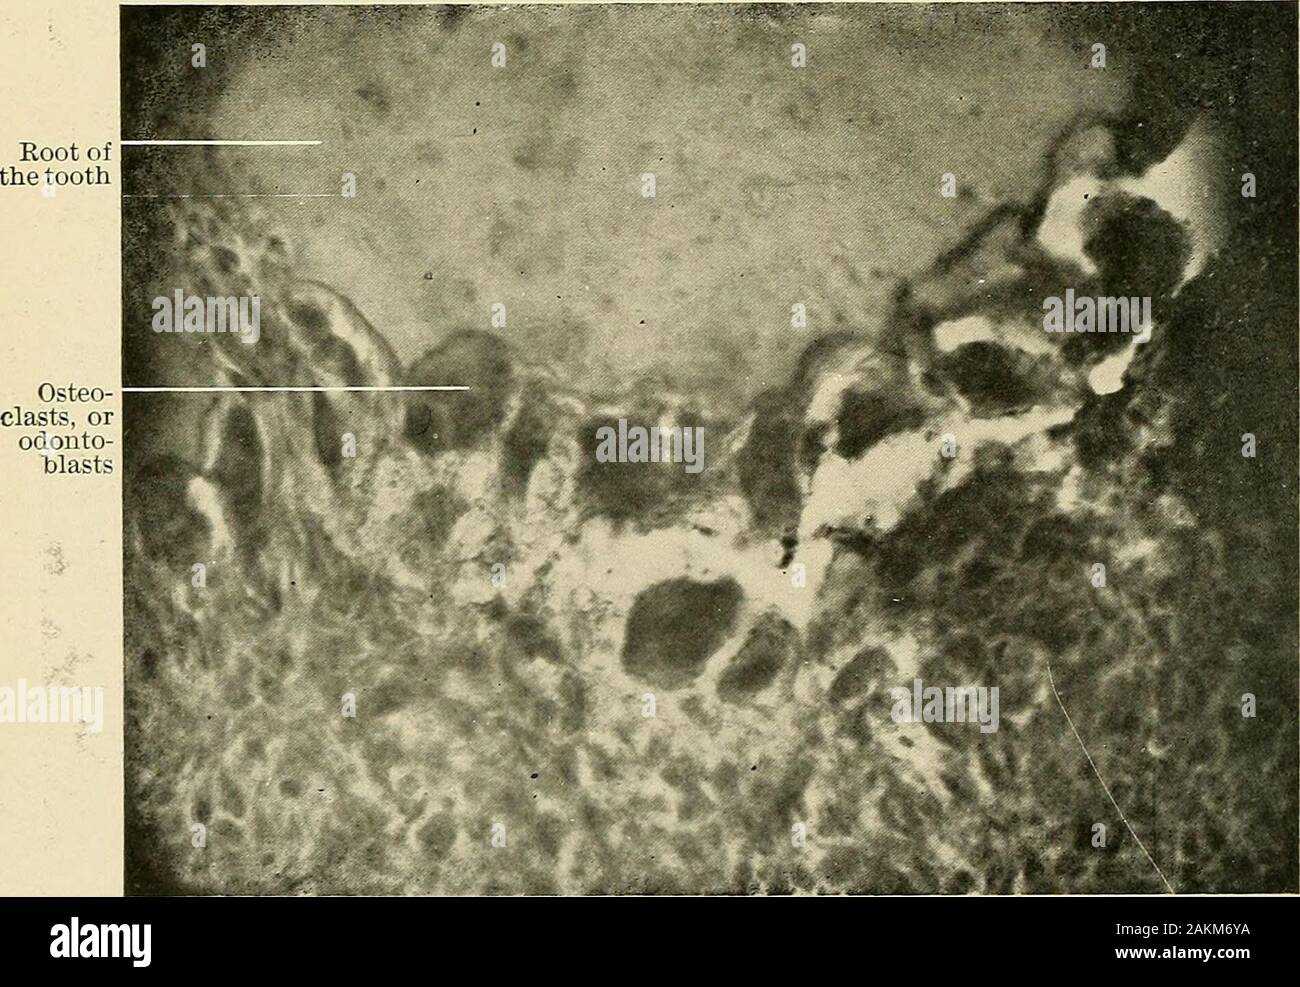

Course Path4172019w2 Case 2 Ubc Wiki

Course Path4172019w2 Case 2 Ubc Wiki

Renal Block 2 Kidney Kidney Disease

Alveolaris High Resolution Stock Photography And Images Alamy

Alveolaris High Resolution Stock Photography And Images Alamy

Alveolaris High Resolution Stock Photography And Images Alamy